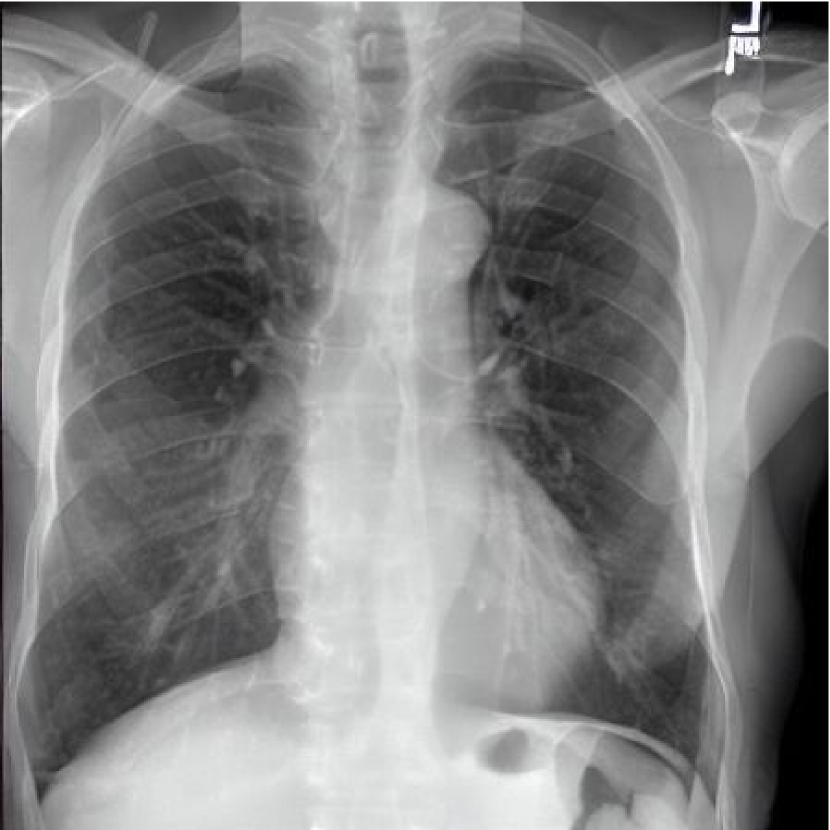

Leveraging Synthetic Data. With the advent of generative modelling tools, we are armed with the power to mitigate the problem of having a long-tail by supplementing the rare labels. We run a small experiment to evaluate whether we can use RoentGen [2], a prompt-based Stable Diffusion model to generate realistic chest X-rays and augment the training data. We generate about 5000 X-rays for training containing at least one pathology from the tail classes. We curate prompts for RoentGen by translating the Spanish reports available in the PadChest dataset to English, and also generate radiologist report-like prompts using ChatGPT 111chat.openai.com by providing curated templates. Figure 3 shows examples of prompts and the corresponding synthetic X-rays generated by RoentGen and verified by a radiologist.

Contribution of Synthetic Data. Figure 2 shows the increase in performance of the model over Table 1. This model was jointly finetuned on MIMIC CXR and a small synthetic dataset (refer Figure 3 for samples). Although the size of the synthetic dataset was too small for it to demonstrate an appreciable performance delta, these results show the promise of leveraging synthetic data to overcome the challenge of training on rare classes at least to some extent, especially since the biggest change is seen in the performance of the tail classes.